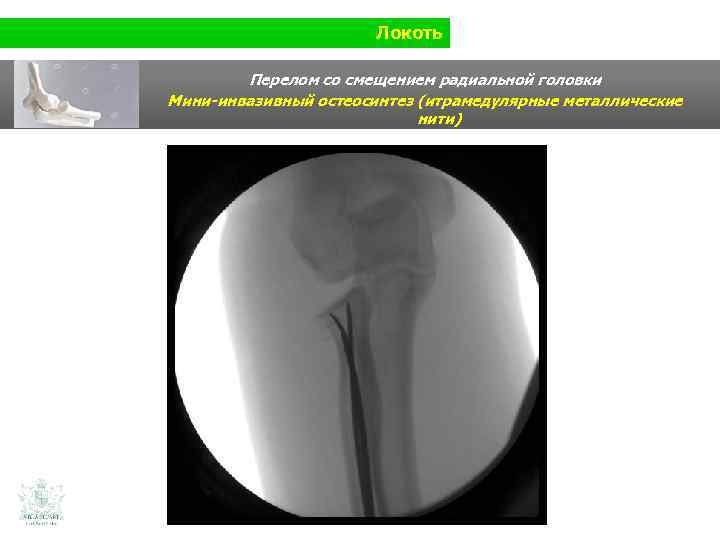

Локоть Перелом со смещением радиальной головки Мини-инвазивный остеосинтез (итрамедулярные металлические нити)